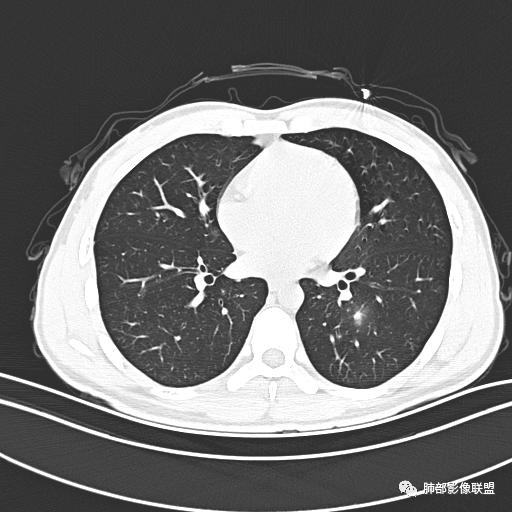

男,19岁

主  诉:发热、全身皮疹2天。

现病史:患者源于2天前受凉后出现发热,最高体温为38.5℃,且颜面部出现少量皮疹,无鼻塞、流涕、咳嗽、咳痰,未在意而未作特殊处理,次日全身皮疹逐渐增多至全身,伴轻度瘙痒,在当地卫生所给予抗病毒、抗感染治疗(具体用药不详)体温有所下降,但皮疹无明显消退,无腹痛、头痛,食欲无明显减退,为进一步诊治,遂于今日急来我院求治,患者目前精神尚可,体力正常,食欲正常,睡眠正常,体重无明显变化,大便正常,排尿正常。

小强:青年,发热,皮疹;双肺散在结节,周围磨玻璃,点晕征,疱疹病毒感染,鉴别荚膜组织胞浆菌,结核。 大雄:青年,急性起病,发热伴全身皮疹2天,抗病毒治疗体温有下降。双肺随机分布大小不等类圆结节,“点晕征”。考虑水痘-疱疹病毒(VZV)血播询问接触史,查体皮疹分布以及形态基本可诊断。 王开金江津中心医院呼吸科:青年男性,起病急,病程短,以发热,皮疹为首发症状,感染指标以单核细胞升高为主,胸部ct双肺多发结界,周围有晕,点晕表现,随机分布,同意於老师意见,水痘疱疹病毒血流感染累及肺。 王秀仙:双肺多发大小不等结节,周围有晕,边缘模糊,呈点晕征表现。青年,急性起病,发热伴全身皮疹2天,抗病毒治疗体温有下降。考虑疱疹病毒。鉴别荚膜组织胞浆菌。 傅昌瑜:19岁男性,发热、全身皮疹2天,单核细胞增高,双肺多发结节,结节边缘见边界不清磨玻璃影。点晕征+发热、全身皮疹+单核细胞增高——考虑水痘-带状疱疹病毒肺炎。 一切∮随缘:年轻男性,发热,皮疹两天,实验室,CRP,PCT增高,影像:双肺多发散在磨玻璃结节,边界欠清,大小不等,呈点晕征改变,以血管束周围分布为主,局部血管束略增粗,其它无明显改变,考虑:1:病毒性肺炎(水痘疱疹病毒?不知道皮肤有无改变)2:真菌(组织胞浆菌,血管侵袭性肺曲霉)3:GPA4:寄生虫(实验室没有看到嗜酸细胞增高) 赵山河:双肺散在结节,周围有晕,边缘模糊,呈点晕征表现。青年,急性起病,发热伴全身皮疹2天,抗病毒治疗体温有下降。考虑水痘—疱疹病毒感染。洪桥爱:青年男性,发热、皮疹2天,伴瘙痒,皮疹于面部首发,之后进展至全身,虽然没有对皮疹进行描述,但是从出疹时间及皮疹进展情况,伴瘙痒,应该就是个水痘患者;CT提示双肺随机分布结节影,部分结节伴有边界不清晕征,考虑水痘血播肺。 刘强:年轻男性,急性起病,皮疹,发热,抗感染治疗体温下降,说明有效。影像表现为散在点晕征,感染类疾病谱(疱疹病毒,真菌,结核),结合年龄,皮肤皮疹,考虑水痘-疱疹病毒性肺炎。 小兜:男性,19岁,发热皮疹两天,颜面部至全身,CRP,降钙素及单核增高。CT示双肺散在小结节,周围伴磨玻璃影,点晕征,考虑为水痘-带状疱疹病毒(varicella-zoster virus,VZV)肺炎 必有路:青年,皮疹+发热+“点晕征”→水痘-疱疹病毒(VZV) 许慧良:青年男性患者,发热、皮疹2天,体温最高38.5℃,第3天皮疹扩展至全身,伴瘙痒,胸部CT:双肺多发随机分布的小结节,结节周边见边界模糊的晕征,考虑水痘病毒感染流心明智:男,19,急性起病,发热伴全身皮疹2天。出疹顺序头→全身,抗病毒有效。胸部CT:两肺多发大小不等类圆形实性小结节影,随机分布,结节周围环绕GGO,边界模糊,呈点晕征。出疹特点是关键,未提示。考虑:血播病毒性肺炎,水痘-疱疹病毒?麻疹?鉴别荚膜组织胞浆菌、TB、血管炎、寄生虫等。 浪迹天涯:病灶多为5-10mm大小结节,结节周围可见磨玻璃样的晕环,常多发,可分布于肺内任何区域,考虑水痘—带状疱疹病肺炎如果短时间内有新的一个区域浸润,更加能说明,